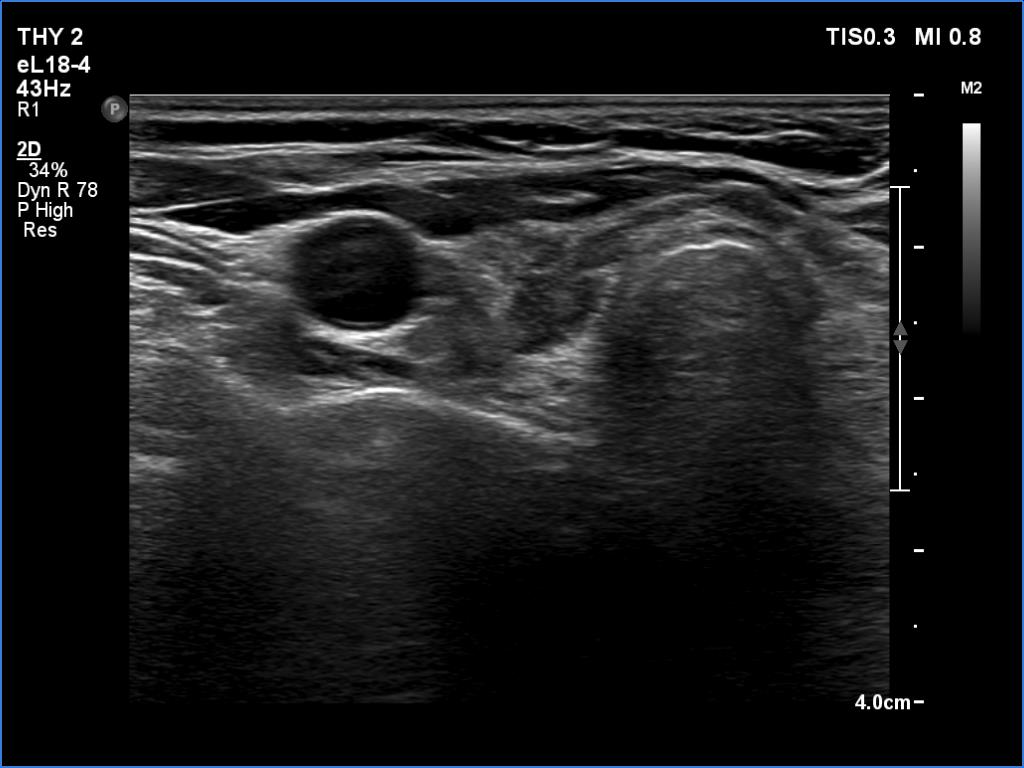

Ultrasonography. The thyroid was atrophic and hypoechoic. There was a hypoechoic mass under the lower pole of the left lobe.